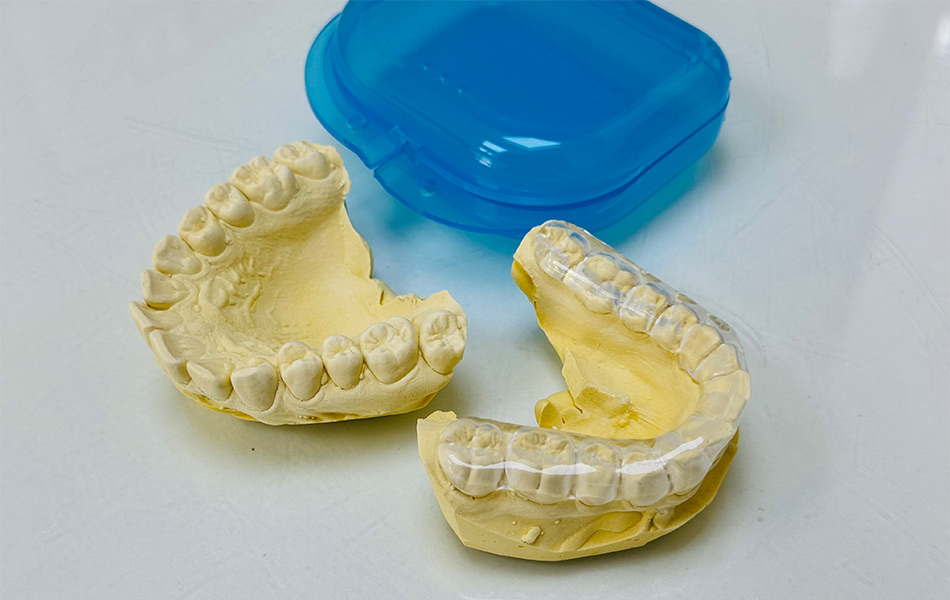

- Ограничение подвижности челюсти — специальные шины или сплинты для расслабления мышц;

- Рентгеновские снимки (КТ, ОПТГ) суставов с описанием.